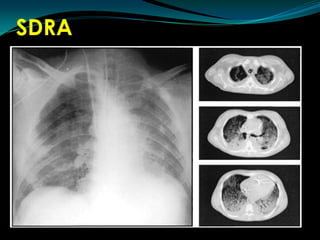

SDRACriterios de DiagnósticoINICIO AGUDOINFILTRADOS BILATERALES RXPRESION CAPILAR PULMONAR < 18 mm Hg.No signos  clínicos de ICCPaO2 / FIO2 < 200

TAC

SDRACriterios de DiagnósticoINICIOAGUDOINFILTRADOS BILATERALES RXPRESION CAPILAR PULMONAR < 18 mm Hg.No signos clínicos de ICCPaO2 / FIO2 < 200